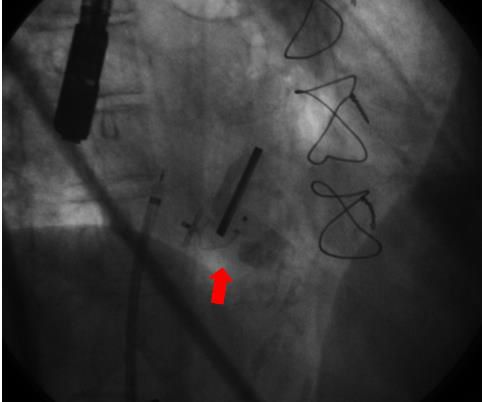

Para el implante, realizado en sala de hemodinamia, bajo anestesia general y guiado por ETE, se utiliza un abordaje mixto transapical y retrógrado-transfemoral implantándose exitosamente un dispositivo AMPLATZER Vascular Plug II.